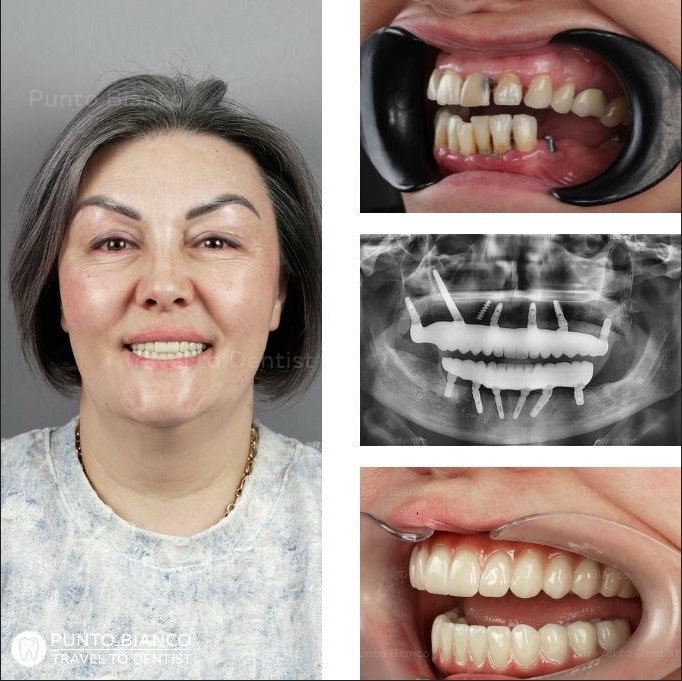

Reabilitare totală cu implanturi speciale

Problema

Pacienta, originară din România și stabilită în Canada, a ales să vină în Moldova la recomandarea unui cuplu mulțumit de rezultatele obținute la Punto Bianco. La momentul prezentării în clinică, situația dentară era una complexă: purta o lucrare veche din metaloceramică, deteriorată și inestetică, iar dinții restanți erau afectați de boală parodontală, prezentând mobilitate. În plus, la nivelul maxilarului superior se constata o atrofie osoasă severă, ceea ce complica semnificativ opțiunile de tratament.

Soluția

În acest caz complex, tratamentul a fost realizat sub anestezie generală, utilizând implanturi clasice, pterigoidiene, zigomatice și un implant scurt în zona inferioară stângă, adaptat osului disponibil. Unii pacienți se pot întreba de ce au fost inserate implanturi și în zone fără dinți vizibili. Acestea au rolul de a stabiliza întreaga structură, în special implanturile zigomatice, și de a oferi suport suplimentar lucrării definitive, asigurând rezistență și durabilitate pe termen lung.

Durata

Prima etapă a durat 9 zile, deoarece a inclus nu doar intervenția propriu-zisă, ci și o pregătire completă și atentă: analize de sânge, investigații imagistice, consultația cu medicul anesteziolog și planificarea detaliată a implanturilor speciale. După perioada de integrare, a doua etapă a durat 11 zile, cu câteva zile în plus față de protocolul obișnuit, pentru a permite întărirea lucrării definitive cu o bară de susținere și a asigura o rezistență optimă pe termen lung.